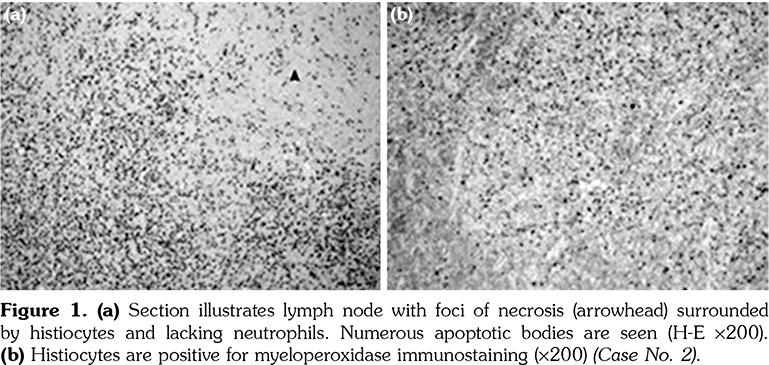

The excised cervical LNs of the 11 patients showed variable degrees of necrotizing lymphadenitis with foci of necrosis surrounded by histiocytes that are positive for CD68 and myeloperoxidase. The histopathology of the excised LN for patients numbered 2, 3, and 7 is illustrated in Figures 1, 2 and 3, respectively.